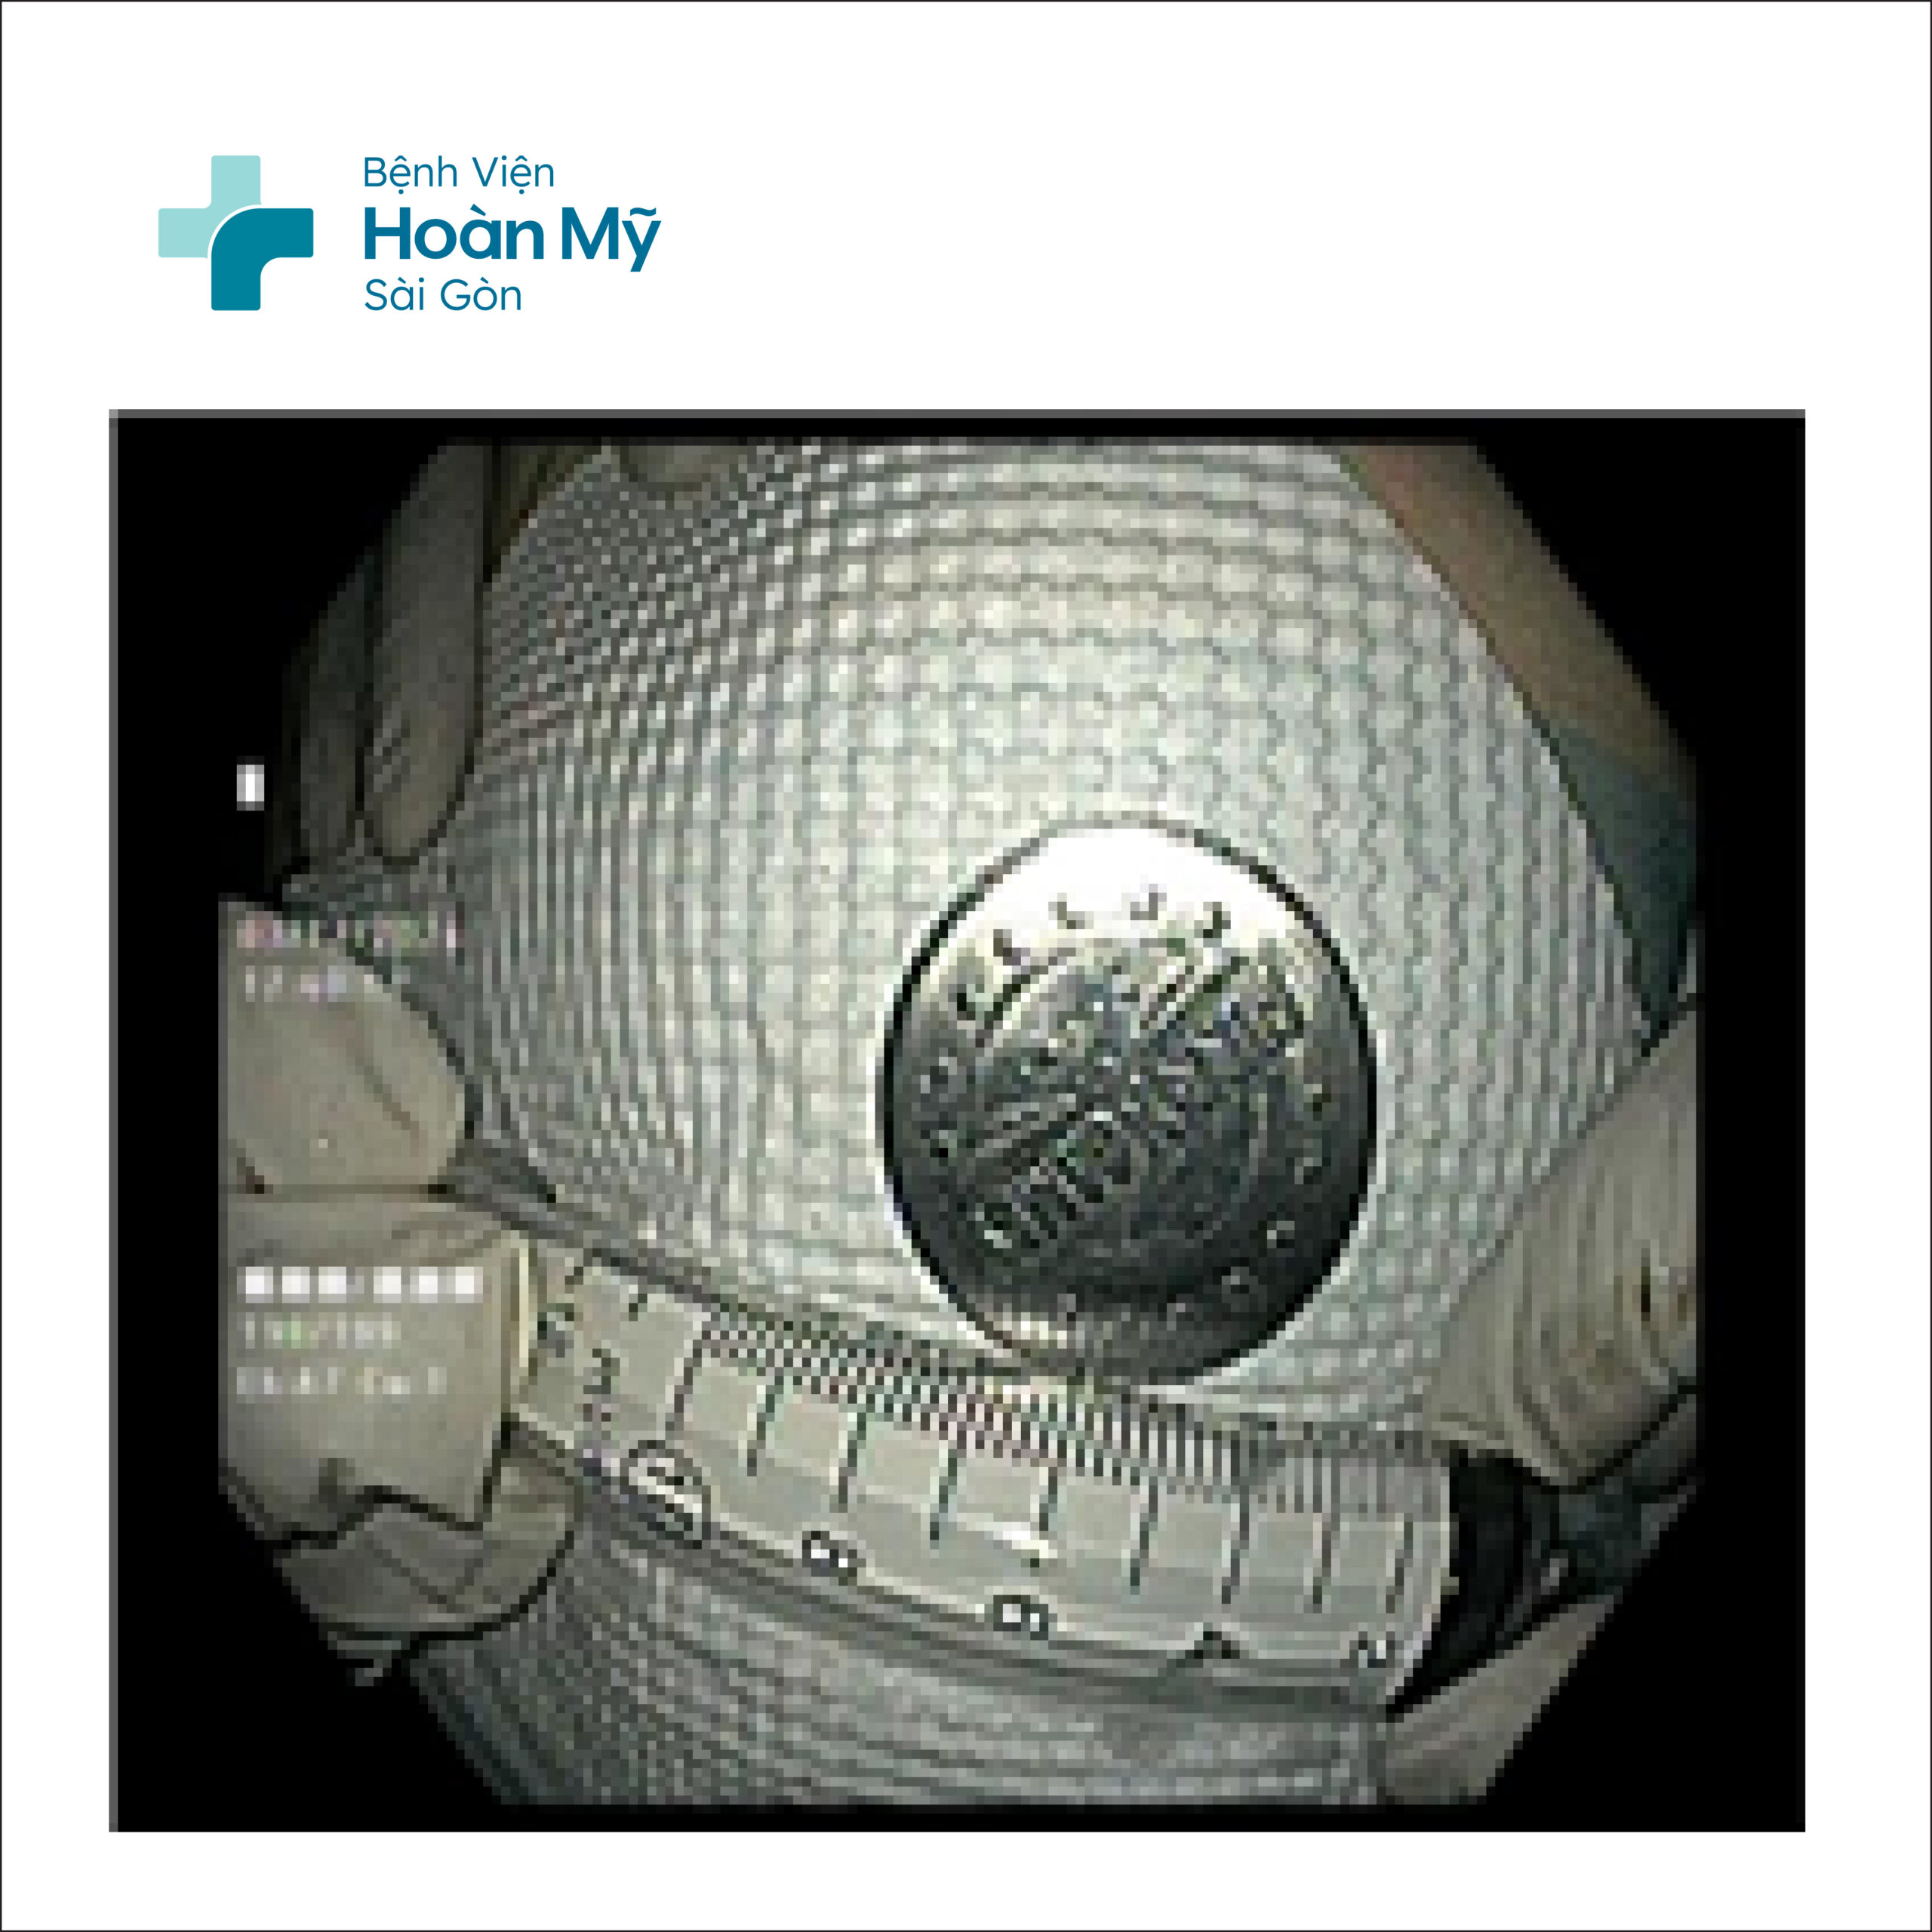

Dị vật nằm trong lòng dạ dày

Dị vật được gắp ra từ dạ dày người bệnh